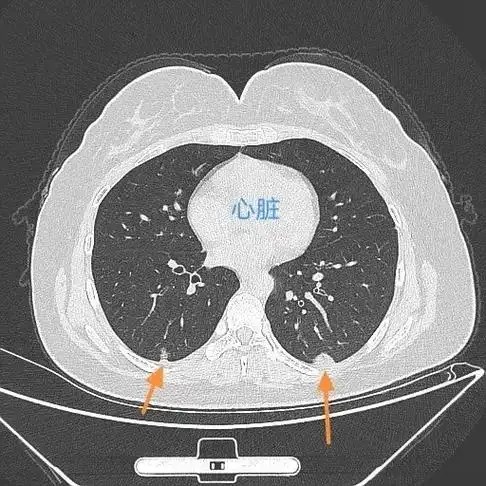

新冠肺炎吸收期 这位女士28岁, 发热,咳嗽,咽疼10天,要 - 抖音